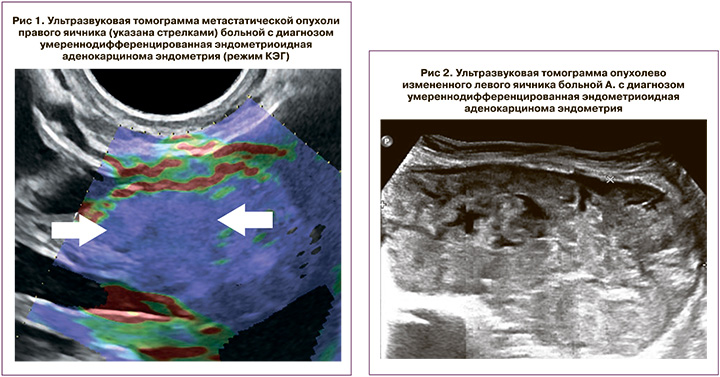

Отметим, что при проведении КЭГ в представленных случаях при метастатическом поражении яичников солидные участки картировались преимущественно 5 типом эластограммы (компонент высокой жесткости) (рис. 1). В солидно-кистозных образованиях в случаях синхронного поражения солидные участки картировались преимущественно 4 типом эластограммы (в равной степени встречались как жесткие, так и эластичные участки).

При УЗИ: Печень без очаговых изменений. Большой сальник утолщен, бугристый, метастатически изменен, толщиной 2,2–2,5 см. Матка увеличена, размеры тела 8,0×6,0×8,5 см, контур ровный, с остаточными признаками аденомиоза, из-за которого граница эндометрия отчетливо не визуализируется. В нижней трети тела и просвете цервикального канала определяются солидные структуры толщиной до 2,0 см, нижний полюс которых визуализируется на 1,5 см выше уровня наружного маточного зева. По левому ребру шейки матки определяется образование диаметром 5,0 см (УЗ-картина соответствует шеечной миоме). Над маткой слева определяется солидно-кистозное образование с четкими неровными контурами, размерами 20,0×18,0 см, в его структуре определяются перегородки и кистозные полости, в которых визуализируются множественные солидные сосочковые структуры, в перегородках и сосочковых структурах определяются локусы патологического кровотока при ЦДК и ЭД (рис. 2). Правый яичник не увеличен, солидной неоднородной структуры, с четкими неровными контурами, размерами 2,2×1,2 см, с единичными локусами патологического кровотока при ЦДК и ЭД (рис. 3), рядом определяется параовариальная киста диаметром 2,0 см. Выявлена свободная жидкость в области малого таза (+3,6 см). Заключение: Опухоль яичников (сложно дифференцировать между первичной опухолью и метастатической). Опухоль матки (следует дифференцировать между опухолью цервикального канала и тела матки). Метастазы в большом сальнике. Асцит. Нельзя исключить первично-множественную опухоль.

Представленный нами клинический пример наглядно демонстрирует отличия ультразвуковой картины метастатически пораженного яичника при РТМ и синхронной опухоли контралатерального яичника. Многолетний опыт позволил нам выделить некоторые отличия ультразвуковой картины при метастатическом и синхронном поражении яичников при РТМ, что помогает в повседневной практической деятельности. При синхронном РТМ и яичников структура опухоли яичников чаще солидно-кистозная с неровными четкими контурами, размеры яичников превышают 6,0 см, при проведении эластографии яичники картируются преимущественно 4 типом эластограммы. При метастатическом поражении опухоли яичников чаще представлены солидными образованиями с четкими ровными контурами, размеры яичников не превышают 6,0 см или не отличаются от неизмененных, а при проведении эластографии солидные образования в структуре яичников картируются преимущественно 5 типом эластограммы [10].